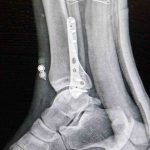

Ortopedi polikliniklerine en sık ayak bileği, diz ve omuz yaralanmalarıyla başvurulduğunu belirten Demirbaş, futbol nedeniyle yaralanma oranlarının da ilk sırada yer aldığını söyledi. Konuya ilişkin Demirbaş, “Futbolda menisküs yırtıkları, ön çapraz bağ yırtıkları, iç ve dış yan bağ yaralanmaları, aşil tendon kopmaları ve ayak bileği bağ yaralanmaları çok sık görülüyor. Ayrıca spora bağlı kırıklar da önemli bir yer tutuyor” ifadelerini kullandı.